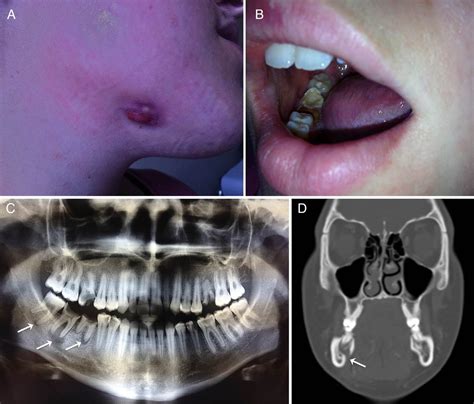

• Formation of a sinus tract (a small pimple-like bump on the gum that may release pus).

When you visit a dentist or an oral surgeon, they will perform a physical examination to check for tender areas, redness, and swelling. However, a clinical exam is rarely enough to confirm a diagnosis. Professionals typically rely on imaging and laboratory tests to confirm a jaw bone infection.

Diagnostic Tool Purpose

X-rays To identify bone changes or large abscesses.

CT Scan Provides detailed 3D views of the bone structure.

MRI Excellent for detecting soft tissue inflammation.

Blood Tests To check for elevated white blood cell counts (signs of infection).

Biopsy/Culture To identify the specific bacteria causing the infection.